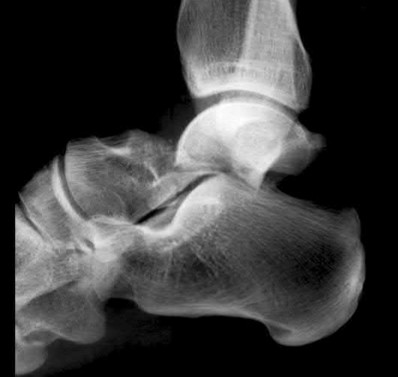

A 25-year-old male sustains an ankle fracture dislocation and undergoes open reduction and internal fixation. He returns to clinic five months following surgery complaining of continued ankle pain and instability with weight bearing. His immediate post-operative AP radiograph is seen in Figure A. Which of the following could have prevented this patient from developing persistent pain?

The patient presents with continued ankle pain and instability following open reduction and internal fixation. The radiograph in figure A demonstrates inadequate restoration of fibular length, likely leading to continued tibiotalar instability.